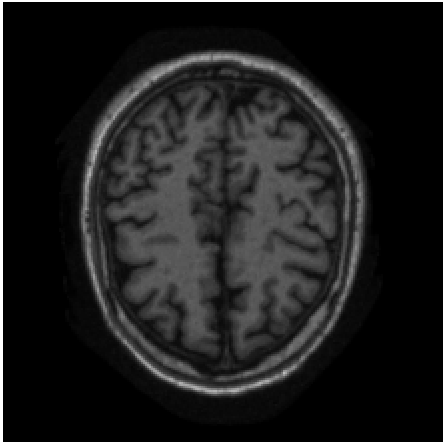

VI-D Semantic Interpolation of Adult Brain MRI

VI-D2 Results

Slice Synthesis: Qualitative evaluation of proposed method on adult brain MRI with reveals that synthesized slices constitute a smooth anatomical transition between neighboring slices. The proposed method is able to bridge large anatomical variations between adjacent slices. These findings are depicted in Figure 12.

Comparison With Conventional Interpolation Method: Qualitative comparison of generated axial brain MRI slices between cubic B-spline interpolation and proposed approach shown in Figure 13 reveals that the proposed method can synthesize excluded axial slices with higher image quality than conventional interpolation method. Moreover, visual inspection of coronal and sagittal slices shown in Figure 13 conveys that images generated by cubic B-spline interpolation more frequently suffer from aliasing artifacts than images generated by our proposed method.

In line with results reported for cardiac cine and neonatal brain MRI in Sections VI-B and VI-C, respectively, quantitative evaluation in terms of SSIM, PSNR, and VIF depicted in Figure 14 corroborate the qualitative findings. Measures were computed on sagittal slices through volume. The proposed method outperformed cubic B-spline interpolation and the differences are statistically significant (p<0.0001𝑝0.0001p<0.0001) in terms of SSIM and PSNR for all upsampling factors (K{2,3,4,5,6}𝐾23456K\in\{2,3,4,5,6\}).